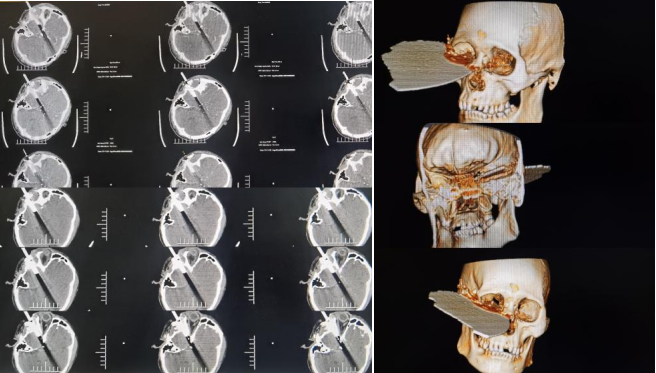

患者入院时烦躁,意识模糊不对答,右侧头面部嵌入断裂切割锯,伤口从右颞经右眼眶底延伸至右鼻根,断裂切割锯一直嵌留于右侧头面部,伤口伴有活动性出血及脑脊液漏,双侧眼睑肿胀,睁眼困难。患者转入神经外科二病区后,科室高度重视,神经外科二病区付登礼教授团队立即组织抢救,初步诊断为开放性颅脑损伤中型、右额颞叶脑挫伤并脑内血肿、创伤性蛛网膜下腔出血、右额颞顶硬膜下血肿、左额颞硬膜下血肿、颅底骨折、颜面部开放性损伤。

时间就是生命,神经外科二病区立即为患者开放绿色通道,迅速指导家属办理入院手续,完成病史采集、体格检查,专人固定患者头部避免异物造成二次伤害,陪同患者完成相关CT扫描三维重建等相关影像学检查,明确患者病情,并组织眼科、耳鼻咽喉科、整形外科等相关科室对该患者进行联合会诊,完善术前准备。

颅内异物贯通伤通常受伤急、病情危重,容易感染、休克等,若处理不及时病死率高,该患者异物停留时间超过10小时,若不及时取出异物,患者生命将面临巨大风险。经多学科会诊共同评估手术风险并制定合理的手术计划后,患者于22:57分完善术前相关准备送入手术室实施“右侧额颞叶脑内血肿清除术、颅内异物取出术、开颅脑清创术、右侧眼眶及颜面部清创术”。

异物刺破患者硬脑膜进入颅内,脑出血、脑组织外漏,有脑脊液流出,大量破碎异物残留于皮下、颞肌及脑组织内。整个手术风险性高、难度大,神经外科二病区张崇进医生在付登礼主任指导下通过显微镜辅助彻底清除脑内血肿,同时清除异物周围挫伤脑组织、残留异物碎片及受污染脑组织,沿异物周围仔细探查。眼科医生沿异物刺入处皮肤向眶内进行探查,耳鼻咽喉科医生配合探查鼻腔,确认无大血管受损,张崇进医生再次确认颅内血管与异物无粘连,完整取出嵌入异物,异物取出后未见活动性出血。显微镜下沿异物入颅处再次仔细探查,未见活动性出血。